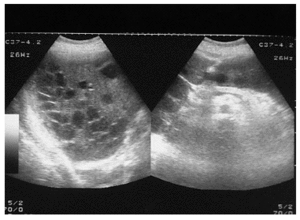

Paciente mujer de 59 años con antecedentes de asma bronquial que ingresa en el servicio de medicina interna por cuadro de malestar general, ictericia, fiebre y mialgias de una semana de evolución. En la exploración física presenta ictericia y hepatomegalia dolorosa, dura y "abollonada" y en la analítica, bilirrubinemia total de 4,7 mg/dl y leucocitosis de 24.000/μl. Se realiza ecografía (fig. 1) y tomografía computarizada abdominal (fig. 2) que muestran hepatomegalia con múltiples imágenes quísticas en el parénquima hepático. Con la sospecha diagnóstica de colangitis y abscesos hepáticos múltiples se decidió una intervención quirúrgica urgente, y se realizó drenaje y lavado de múltiples colecciones, colecistectomía reglada y drenaje de la vía biliar.

Figura 1.